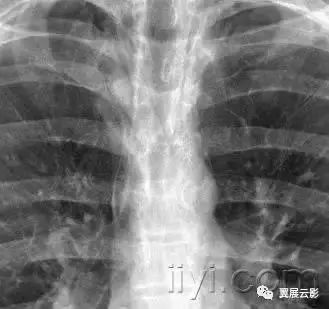

一、急性间质性肺炎

病理:不明原因的弥漫型肺泡病变。急性期特征为水肿和透明膜形成,晚期表现为含气腔隙和/或间质的机化。

病理上难以与急性呼吸窘迫综合征鉴别。平片和CT:急性期显示为双侧片状磨玻璃影,一些小叶可以不受累,产生地图样影像。在机化期,可以有结构的扭曲,牵拉性支扩,网状密度增高影。